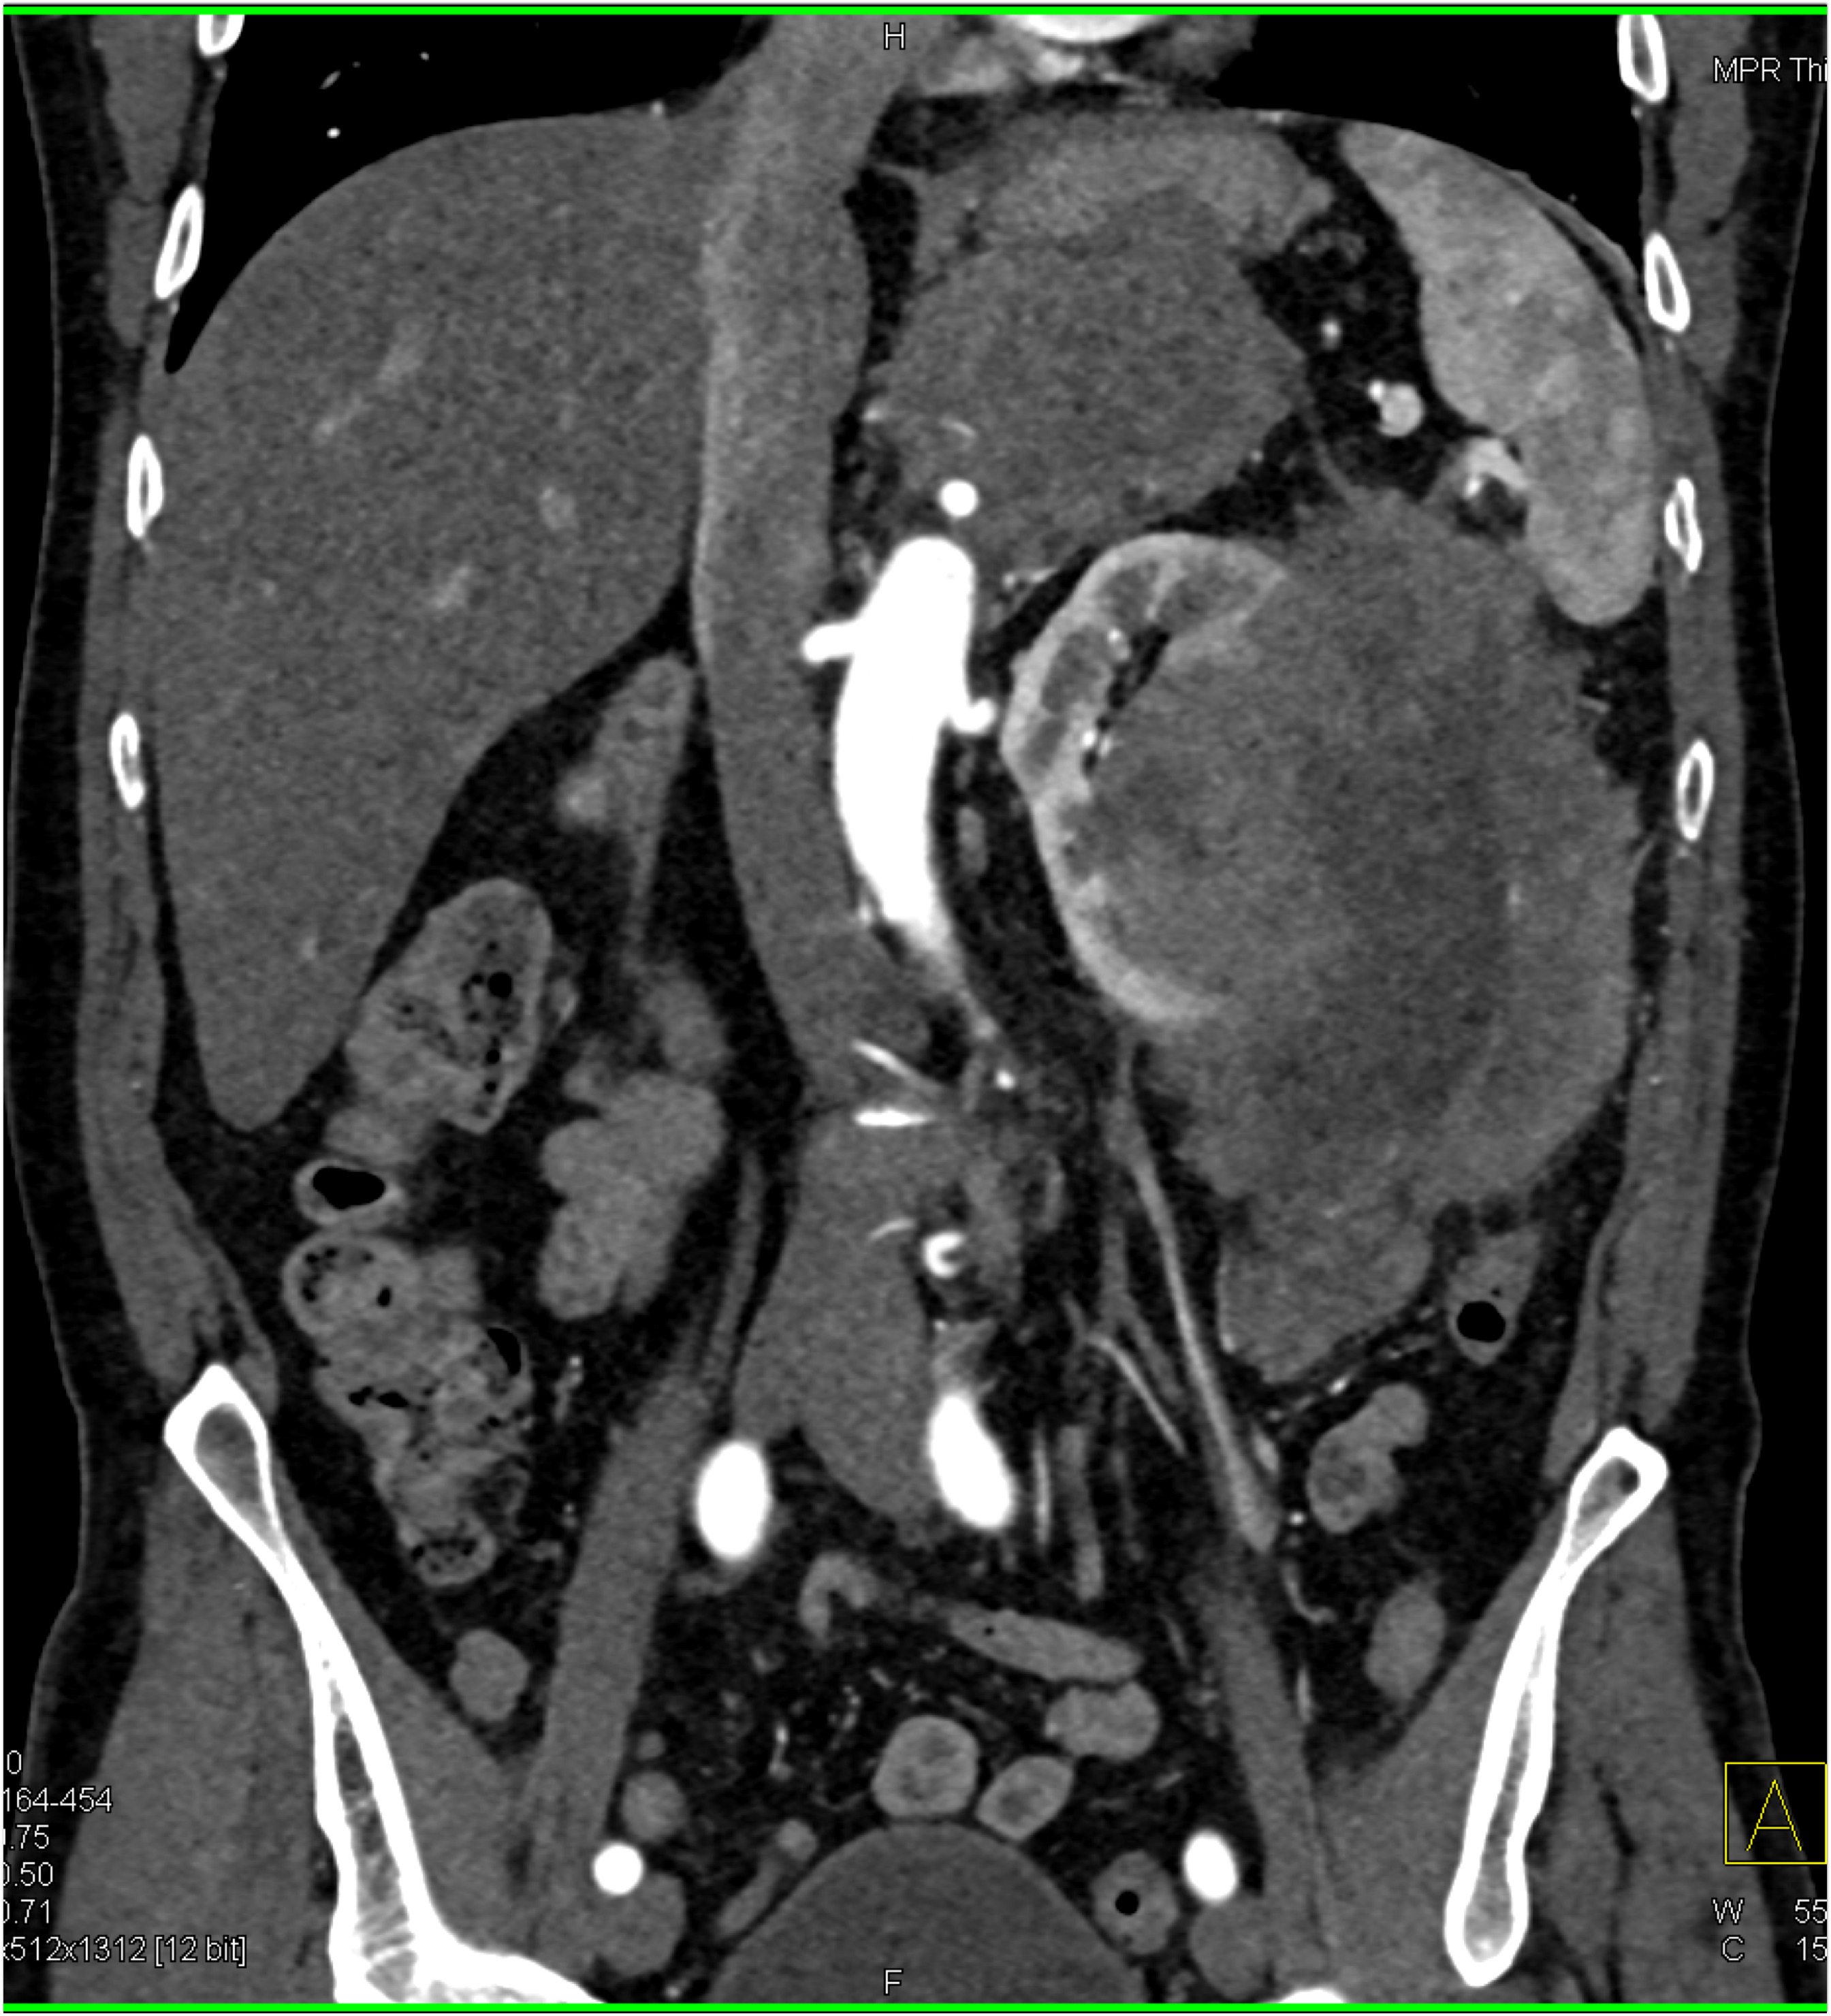

8) The most likely diagnosis in this case is?

clear cell renal cell carcinoma

large B-cell lymphoma

seminoma

renal abscess